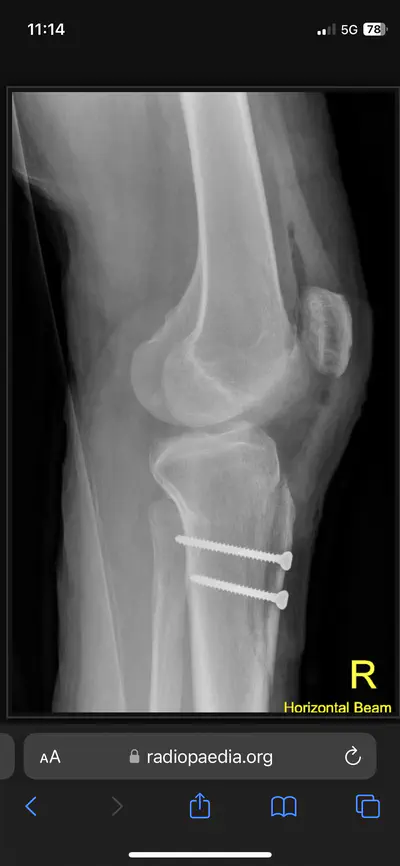

I could have a total knee replacement instead, but replacements don’t last forever and they don’t like to do them more than twice. (Again, same exact scenario I was in with my hip.) In order to preserve my knee joint for another ten to fifteen years, so that I can start getting replacements at a normal age instead of way too young, they’re going to cut out the part of my tibia that the knee tendon attaches to, pull it to one side so my patella will track straight instead of out to the side, and screw that bad boy back in place.

not my actual knee